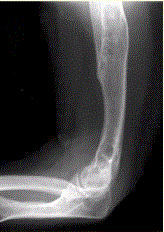

问题 患者男,22岁,长期存在骨和关节变形,近期出现右肘关节疼痛,进行性加重。行右肘关节X线正侧位片检查,见下图。 如患者无家族史,呈单侧发病,智力正常,则首选诊断为

选项 A.内生软骨瘤(Ollier病) B.遗传性多发性外生骨疣 C.神经纤维瘤病 D.进行性骨干发育不良 E.干骺发育不良 F.Albright综合征

答案 A